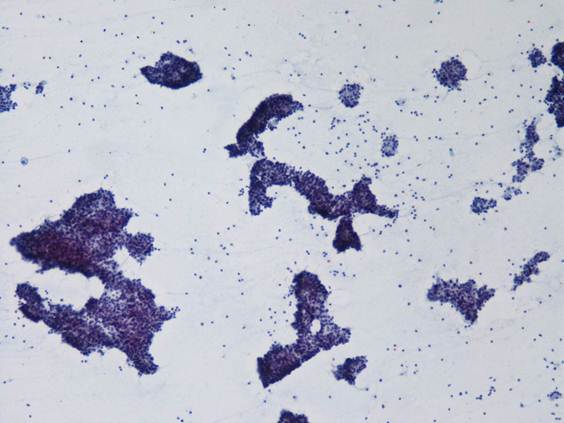

細胞診所見

背景に組織球やライトグリーンに染まる顆粒が認められ、腺房を形成するような形態の細胞集塊が多数出現していた。